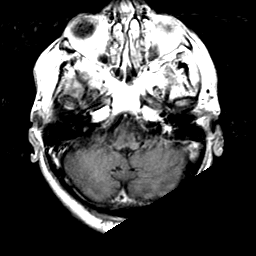

Meningioma, MR Study #1 -- Slice #3

[Home][Help][Clinical] Slice 3